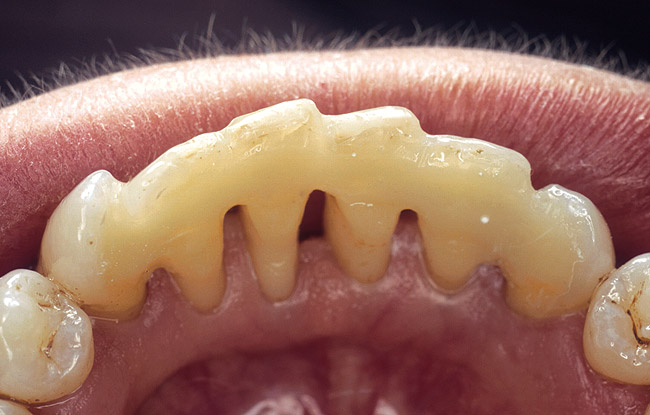

When fiber-reinforcing materials were introduced, the focus for their use was for periodontal splinting and stabilization resulting from tooth mobility.6,10,16,41-43 There is no doubt that splinting does reduce tooth mobility while the splint is in place.44 In the last decade, research supports the use of periodontal splinting as recommended therapy to stabilize those teeth to improve long-term prognosis.45-47 In a long-term clinical evaluation of splinting over a period of 48 to 96 months, using the original Ribbond Reinforcement Ribbon in fiber-reinforced composite resins was highly successful.17 The success of these splints can be attributed to close adaptation of the fiber ribbon to the tooth surface combined with cross stabilization of the mobile teeth by placing adhesive composite resin on the facial surfaces (Figure 4A, Figure 4B, Figure 4C, Figure 4D, Figure 4E).34,35 Splinting of traumatized teeth with fiber-reinforcing materials and adhesive composite resin has also been reported.48,49 When using fiber to stabilize the traumatized tooth or teeth or for tooth stabilization after re-implantation, the tooth must be allowed to have some movement and not be fixed in place.50,51